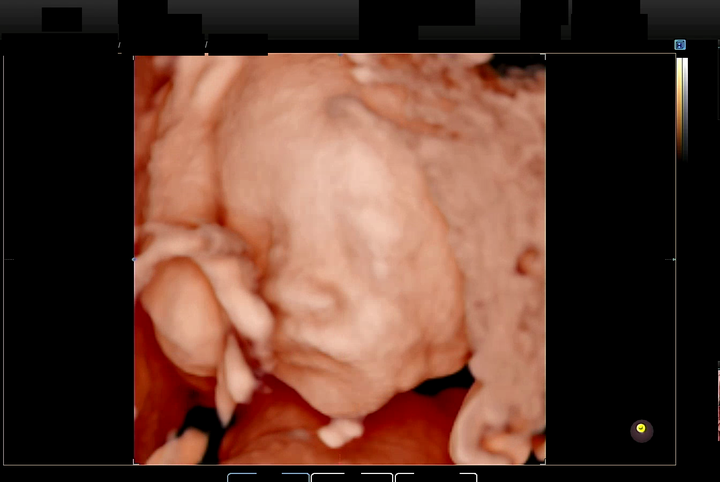

특히, 최근에는 입체 초음파 이미지까지 분류 대상으로 포함시키면서, 총 6개의 클래스로 구분하는 작업을 진행했다.

입체 초음파 데이터를 다루면서 또 다른 문제가 발생했다. 기존에는 3D 초음파에서 제대로 분석이 어려운 영상을 UNKNOWN 으로 분류했지만, 점점 더 많은 데이터를 다루다 보니 입체 초음파 역시 세분화가 필요하다는 것을 깨달았다.

입체 초음파에는 다음과 같은 주요 패턴이 존재했다:

- 눈, 코, 입이 뚜렷하게 보이는 경우

- 이미지가 흐릿하거나 잡음이 많은 경우

- 얼굴의 각도가 정면인지 아닌지

입체 초음파의 경우 색상으로 잘 구분이 되는지 인식도가 높았다. 하지만 테스트를 지속할 수록 눈, 코, 입이 뭉게진 이미지들도 높은 신뢰도로 인식되는 경우가 많았다. 그래서 눈, 코, 입이 잘 보이는 이미지와 흐릿한 이미지를 따로 구분하는 새로운 클래스(three_d_noise)를 추가하기로 했다.

"같은 초음파 영상" 에서 AI 모델이 자동으로 분류한 경우;